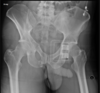

Masculino, 12 anos

Síndrome da sincondrose isquiopúbica assimétrica (Doença de Van Neck-Odelberg)

Variante da normalidade (em geral assintomático)

Crianças

Alargamento e radioluscência na sincondrose isquiopúbica, que simula neoplasias, infecção;